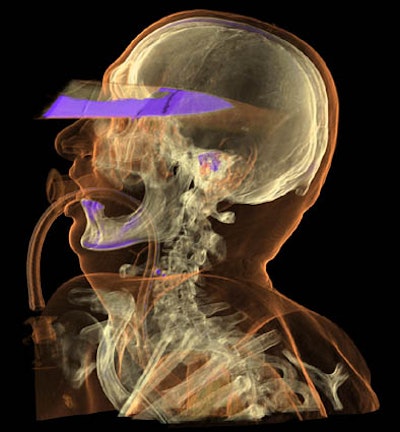

![]() |

| A traffic accident victim suffered from multiple fractures and died from a broken neck vertebra (below). Images courtesy of Dr. Anders Persson and Patric Ljung. |

Air is completely translucent, and serves as a negative contrast agent in postmortem imaging, Persson said in his presentation.